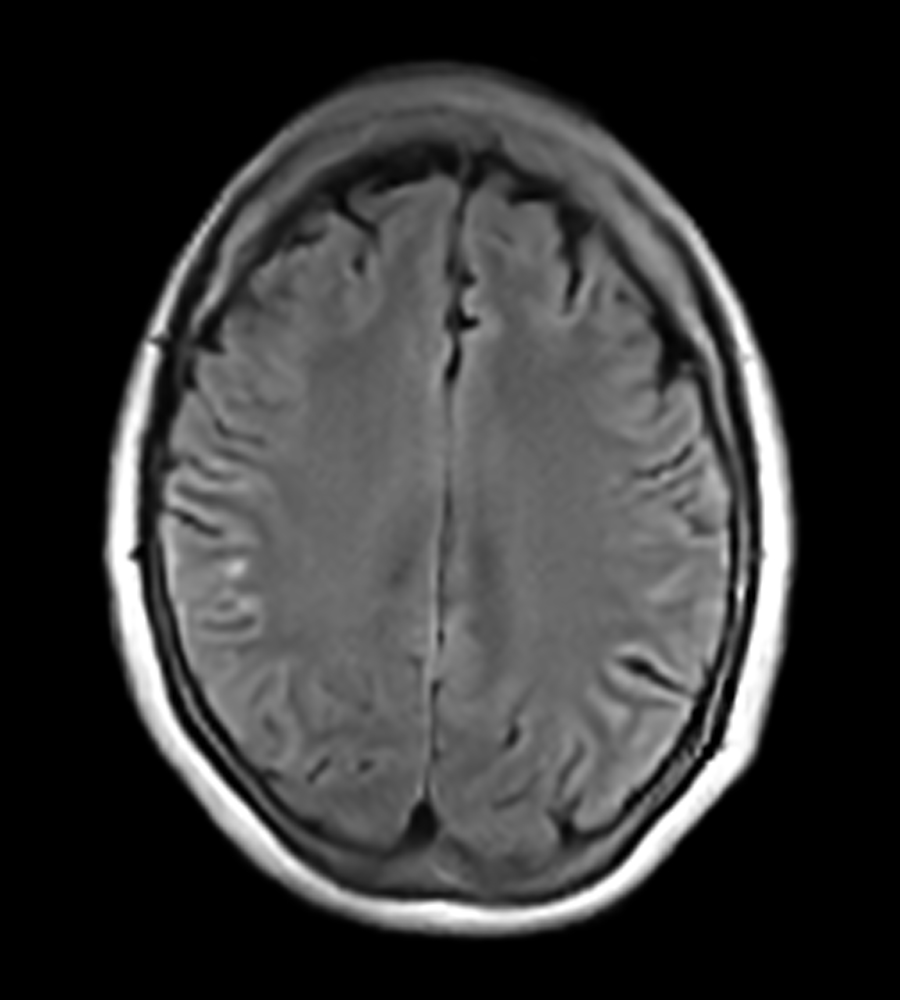

Clinical Images

Clinical Case Types: Headache, Migraine, Multiple Sclerosis, Microvascular Disease, and Tumor Routine Follow-up.

Migraine